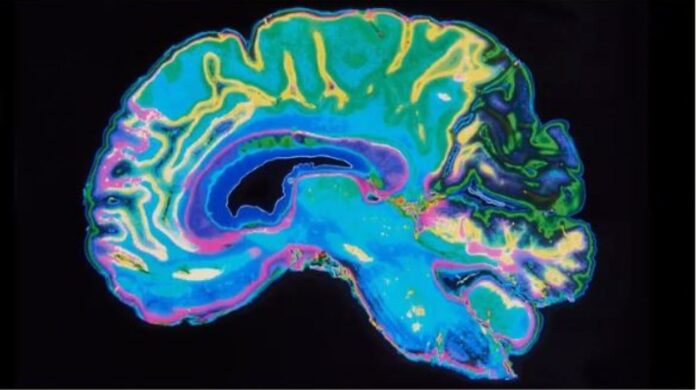

“Desafortunadamente, en México existe un número elevado de enfermos de Parkinson y las estadísticas no reflejan en realidad lo que está ocurriendo. Hay casos que no están atendidos, ni diagnosticados adecuadamente, pero eso no quiere decir que no existan. Y aunque se han desarrollado investigaciones al respecto, la mayoría se ha enfocado en el desarrollo de fármacos que a largo plazo están produciendo toxicidad y empeorando la sintomatología, cuando deberían estar enfocados en estrategias de prevención y en mejorar la calidad de vida de los pacientes”Así lo externó la doctora Margarita Gómez Chavarín, académica e investigadora del Instituto de Investigaciones Biomédicas (IIB) de la Universidad Nacional Autónoma de México (UNAM).Es alarmante que no exista un censo reciente confiable del número de enfermos de Parkinson, el último registro disponible es del 2019 y sólo abarca los años de 2014-2017, y la realidad es que el 30% de la población de México está alcanzando edades avanzadas, así que, como esta enfermedad se asocia con el envejecimiento, inevitablemente la población que podría padecerla seguirá creciendo exponencialmente.Aunado a ello, en México existen muy pocos especialistas que atienden a esta enfermedad conrespecto a su población.Con base en el último censo realizado por la Academia Mexicana de Neurología, en el país existen alrededor de 1,200 neurólogos, lo que nos da la ecuación de unneurólogo por cada 100 mil habitantes.El Parkinson, cabe recordar, es una enfermedad crónico-degenerativa progresiva, incurable e invalidante; se ha demostrado que en su desarrollo participan el estrés oxidativo y la disfunción mitocondrial de las neuronas productoras de dopamina. Cuando la funcionalidad de estas neuronas se reduce considerablemente emergen los problemas motores y no motores, que al presentarse en etapas productivas de la vida producen el paciente gran impacto emocional y socioeconómico.Cabe mencionar que el Parkinson es una patología que puede iniciar 10 a 15 años antes de que aparezcan los síntomas motores, que es el principal parámetro de diagnóstico, estos síntomas pueden iniciar con la pérdida de sueño, cambios de estado de ánimo, tics nerviosos, constipación intestinal y pérdida de olfato, por lo cual es importante que los médicos de primer contacto, estén alertas en la detección de los síntomas tempranos para que generen estrategias de progreso de la degeneración de las neuronas dopaminérgicas y en adultos mayores que no presenten síntomas considerar tomar medidas de prevención.Como parte del grupo de investigación del laboratorio del Dr. Gabriel Gutiérrez Ospina en el IIB, la doctora Gómez Chavarín ha implementado un modelo en rata de la enfermedad de Parkinson, con el uso de la pesticida rotenona, generador de estrés oxidativo e inhibidor del funcionamiento mitocondrial. “Una vez inducidas las características parkinsónicas en los roedores, con la administración vía oral de Omega-5 Nanoemulsionado conseguimos que la mayoría de las ratas con daños motores mejoraran la ejecución de pruebas motoras a las que fueron sometidas,disminución de la oxidación de lípidos y de la producción de la proteína α-sinucleína, así como el aumento de la concentración de dopamina en una estructura cerebral conocida como núcleo caudado, encargada de modular las funciones motoras. Adicionalmente no encontramos alteración en los parámetros útiles en la detección de síndrome metabólico (aumento del peso, triglicéridos, colesterol y glucosa)”.¿Cómo podría el Omega-5 Nanoemulsionado favorecer el funcionamiento de las neuronas dañadas por la rotenona? Como es un potente antioxidante redujo el estrés oxidativo, y quizás, estabilizó la fluidez de la membrana neuronal y de la membrana mitocondrial, en donde se llevan a cabo múltiples señales para el adecuado funcionamiento del sistema nervioso central.Cada vez se tiene mayor conocimiento de los mecanismos que subyacen a esta enfermedad, y es muy alentador que el Omega 5 formulado con nanotecnología haya mostrado estos resultados, por lo cual la propuesta es que este producto por su alta capacidad antioxidante, podría incorporarse como un nutraceútico protector del sistema nervioso central de los daños ocasionados por factores ambientales generadoras de estrés oxidativo y daño mitocondrial, con el fin de disminuir el riesgo de desarrollar enfermedades neurodegenerativas como el párkinson y/o de enfermedades crónicas como diabetes y el síndrome metabólico, así como para mejorar el manejode pacientes con Parkinson al disminuir los síntomas y aumentando la vida media de los fármacos utilizados en su tratamiento.“Actualmente el Dr. Gabriel Gutiérrez Ospina y una servidora, estamos desarrollando undiseño experimental en roedores de neuro prevención y neuro protección con el uso delOmega-5 Nanoemulsionado, que permita disminuir las probabilidades de desarrollarenfermedades que se presentan hasta la edad adulta, que podrían tener un origen durante desarrollo embrionario”, informó la Dra. Margarita Gómez Chavarín.En este contexto, se estima que en el mundo existen entre siete y 10 millones de personas conParkinson y, en México, los cálculos apuntan que 50 de cada 100 mil habitantes pueden padecerla.Por su parte el Doctor Mauricio Veloso, con especialidad en Medicina Interna y Director Médico dela distribuidora BioLife, nos refiere que: “Es un drama para el paciente quien lo padece. Hay doselementos importantes en el Parkinson: el temblor, por un lado, y la rigidez, por el otro, peroademás hay otros signos no motores, que secuestran y van minando la calidad de vida de laspersonas, por lo cual es importante encontrar sustancias, como el Omega 5 Nanoemulsionado, queayudan a detener el avance de la enfermedad”.Añade que este suplemento nutricional coadyuva no solo a retrasar el inicio del Parkinson y elconsecuente consumo de los medicamentos para esta enfermedad, sino que mejora el efecto ONde los fármacos, es decir, aumenta el periodo en el cual estos hace efecto y disminuye el efectoOFF. -